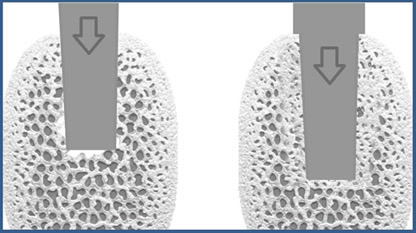

Bone Condensing: ein konisches Instrument wird vertikal so in den Knochen eingebracht, das sich die Kavernen im Knochen verdichten. Es entsteht Knochen mit kleineren Hohlräumen (rechts)

Bei Vorliegen von weichem, weniger dichtem Knochen wird zunächst nur ein kleines Loch gebohrt und das Implantat vorsichtig eingeklopft. Der Vorteil: Es wird weniger Knochenmaterial abgetragen. Der Knochen bleibt erhalten und wird verdichtet. Dieses Verfahren kann dem Implantat einen besseren Halt geben. Zusätzlich ist die Einhaltung einer längeren Einheilungszeit zu empfehlen (6 – 12 Monate im Oberkiefer).